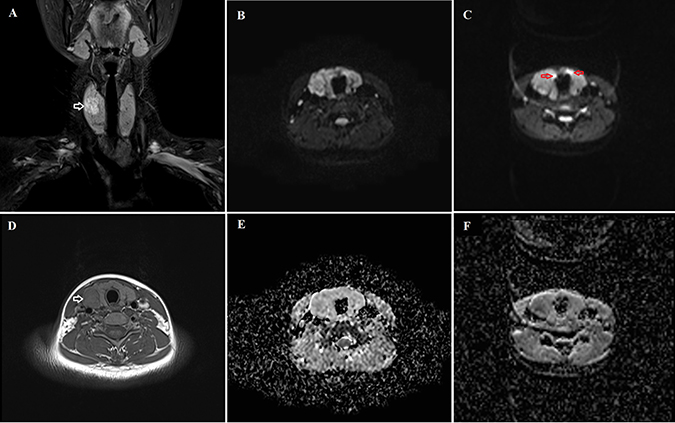

The analysis results of image quality for the iShim-EPI and 3D-Shim-EPI techniques are shown in Table 1. Figure 1 shows example images with iShim-EPI and 3D-Shim-EPI images from a patient with thyroid nodules. For both Observers 1 and 2, the average scores for iShim-EPI were significantly higher than those with 3D-Shim EPI images for susceptibility artifacts (2.81 ± 0.37 vs. 1.93 ± 0.29, p < 0.001), ghost artifacts (2.95 ± 0.15 vs. 1.93 ± 0.29, p < 0.001), and the detectability of thyroid nodules (3.00 ± 0.00 vs. 2.55 ± 0.75, p = 0.008) (Figure 2), respectively.

Figure 1: Comparison of the iShim-EPI and 3D-Shim-EPI sequences in a 26-year-old female with a thyroid nodule in the right thyroid lobe. (A) is a T2-weighted image with fat saturation and (D) is a T1-weighted image. Hyperintensity and hypointensity characteristics of the thyroid nodule were observed on these images (white arrows). The iShim-EPI DWI image had b = 500 s/mm2 (B) and ADC map (E). 3D-Shim-EPI DWI image with b = 500 s/mm2 (C) and ADC map (F). Susceptibility (red arrows) and ghost artifacts are shown on the 3D-Shim-EPI images, whereas improved image quality was observed using the iShim-EPI technique.